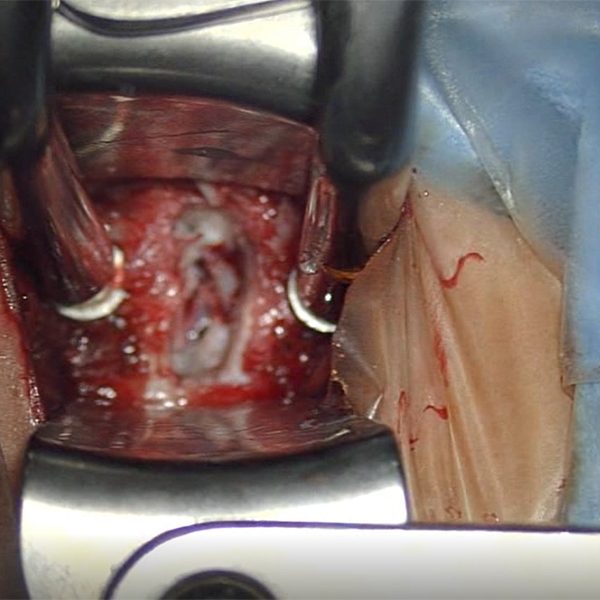

Servikal Disk Hernisi

- Mobilitemi Füzyon mu?

- Servikal Disk Hernisi Tedavi Seçenekleri

- Servikal Disk Protezi Endikasyonları

- Servikal Disk Henrisinde Füzyon

- Servikal Disk Protezinin Avantajları ve Dezavantajları

- Servikal Disk Protezi Kontraendikasyonları

- Servikal Disk Hernisi

- Patoloji

- Cerrahi Yaklaşım